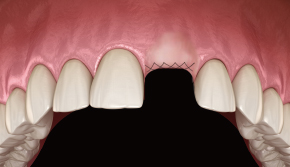

2. 터널 점막 거상

-

3. Bone Carrier로 골이식재 수집